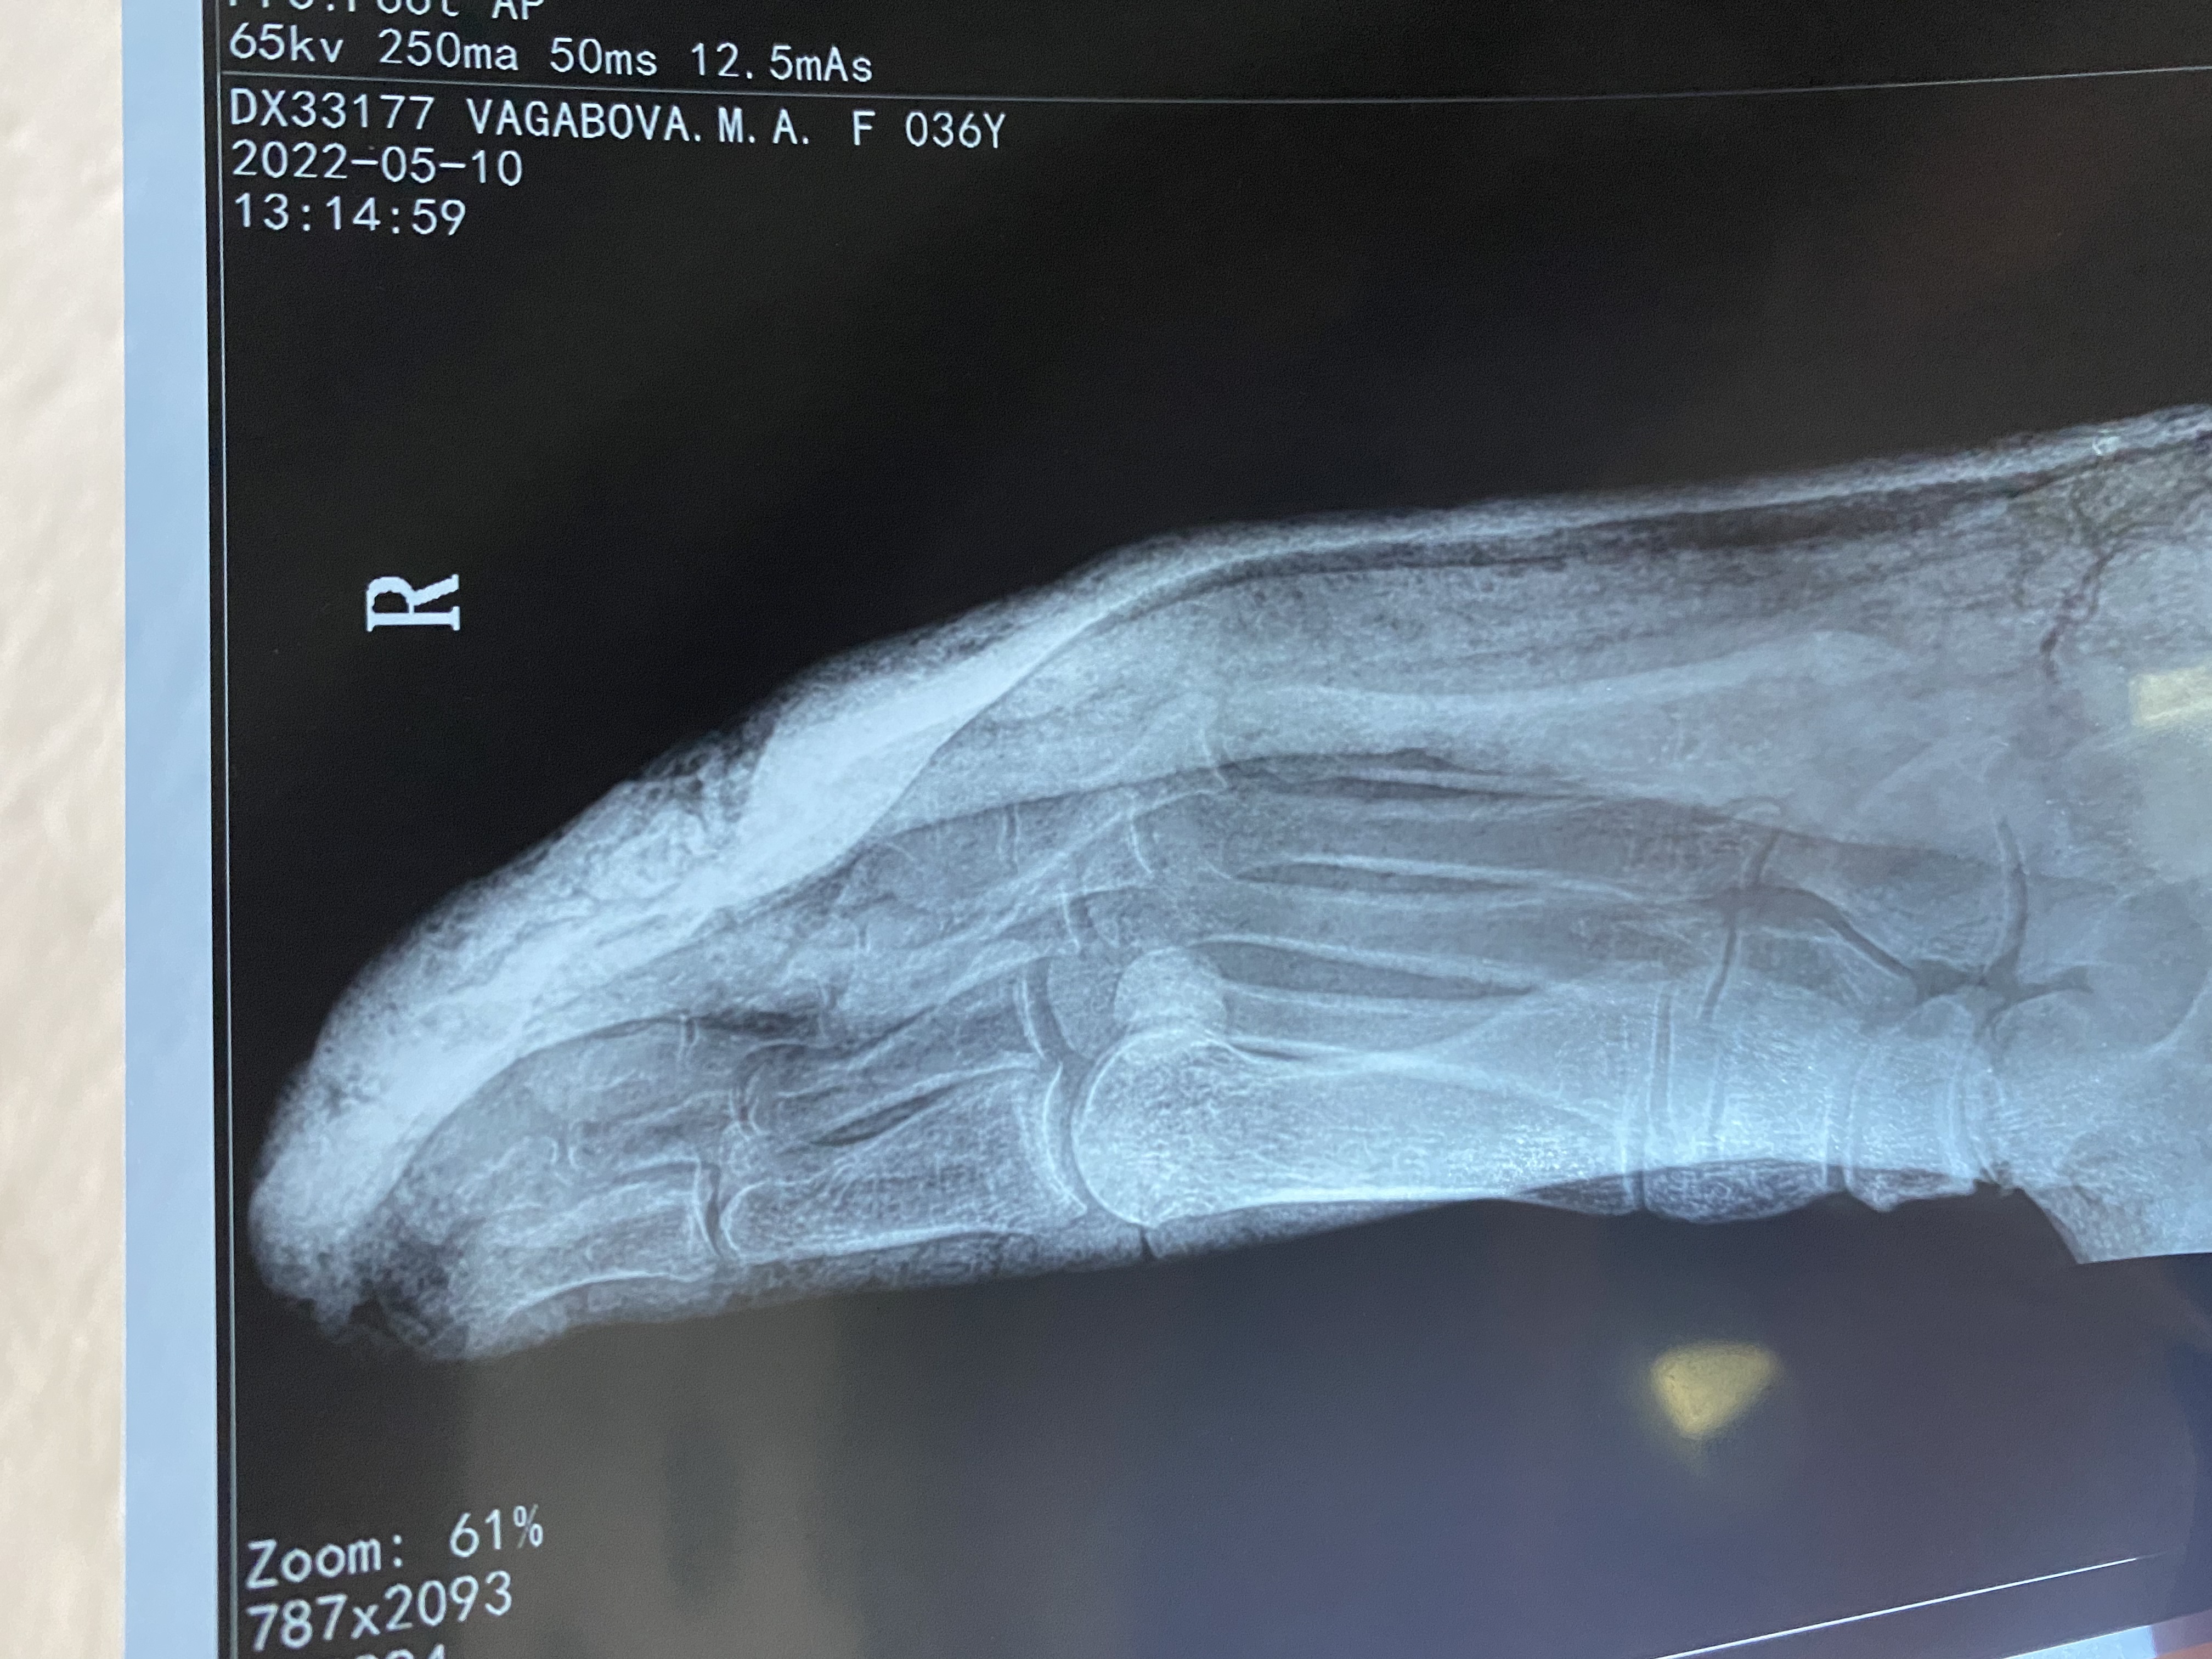

Здравствуйте.Месяц назад был перелом основной фаланги 4 пальца стопы со смещением.Провели репозицию и наложили лонгету. Сделала контр.снимок.Посмотрите пожалуйста снимок и скажите,в какой стадии перелом и сколько носить лонгету и съехал ли палец с места?

Для оценки смещения нужны 2 проекции, для оценки степени консолидации- снимки без гипсовой иммобилизации. Сколько носить расскажет травматолог.

Спасибо, что ответили. Приложила боковой снимок.

Обозначил бы положение как удовлетворительное, заживление можно оценить на снимке через 1-2 месяца. Будет быстрее при щажащем режиме на конечность